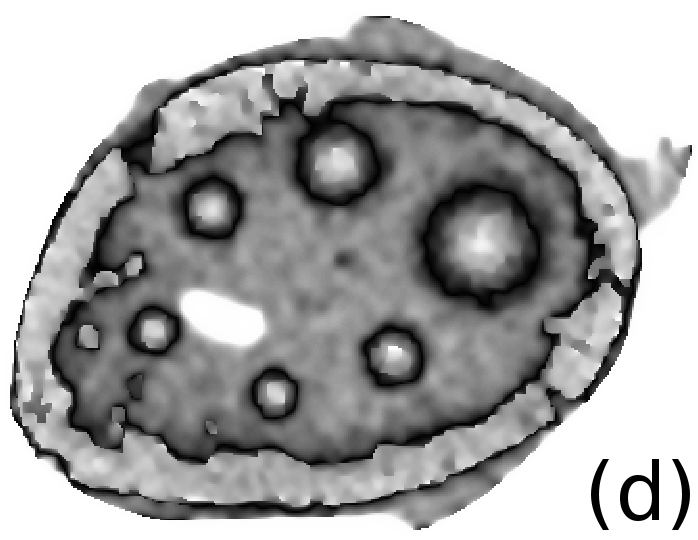

Reconstructed images are presented in Fig. 4. Since CGLS-TV- reconstruction might look more appealing than CGLS-EL we also show the surface representations of reconstructed images (see Fig. 5) and horizontal middle cross-sections (see Fig. 6).

One can notice that CGLS reconstruction is very noisy. CGLS-TV method better suppresses noise, however smooth features are strongly affected by the “staircasing” effect. CGLS-TV- method provides reconstruction with smoother features and CGLS-EL method resolves smooth features even better (e.g. cone-shaped parabola). Although CGLS-EL method performs very well for smooth objects one can notice the wave-like variations of intensity in the background and also at the top of the rectangle (see Fig. 6). This issue can be explained by the properties of our regularizer, in contrast to TV, our penalty does not seek the sparsest solution and does not penalize strongly (pushing to the constant value) a small intensity perturbations. The EL term tends to preserve all sharp edges while uniform noise is smoothed isotropically with the Laplacian. In Fig. 6 one can see that the CGLS-EL method provides better recovery of smooth features while slightly higher (compare to TV and TV-) perturbations visible in uniform areas (the top of the rectangle), however, the edges of the rectangle are defined sharper with the EL penalty.

In Fig. 10 and 11 one can notice that the BR is very smooth for TV and TV- penalties and some long-wave oscillations can be seen in the reconstructed image with EL penalty. This result corresponds to the expected behaviour of the EL penalty. We note here that the phantoms background (see Fig. 7) is not as flat as TV and TV- penalty recovered it. Furthermore, a small size dot-like feature (approximately in the centre of the phantom) is almost smoothed out with TV and TV- recovery. However, it is visible and well recovered with EL penalty. The sharp features, overall, are reconstructed very well with MLEM-EL method and seem even sharper compare to other methods (see the bone outer rim in Fig 10).